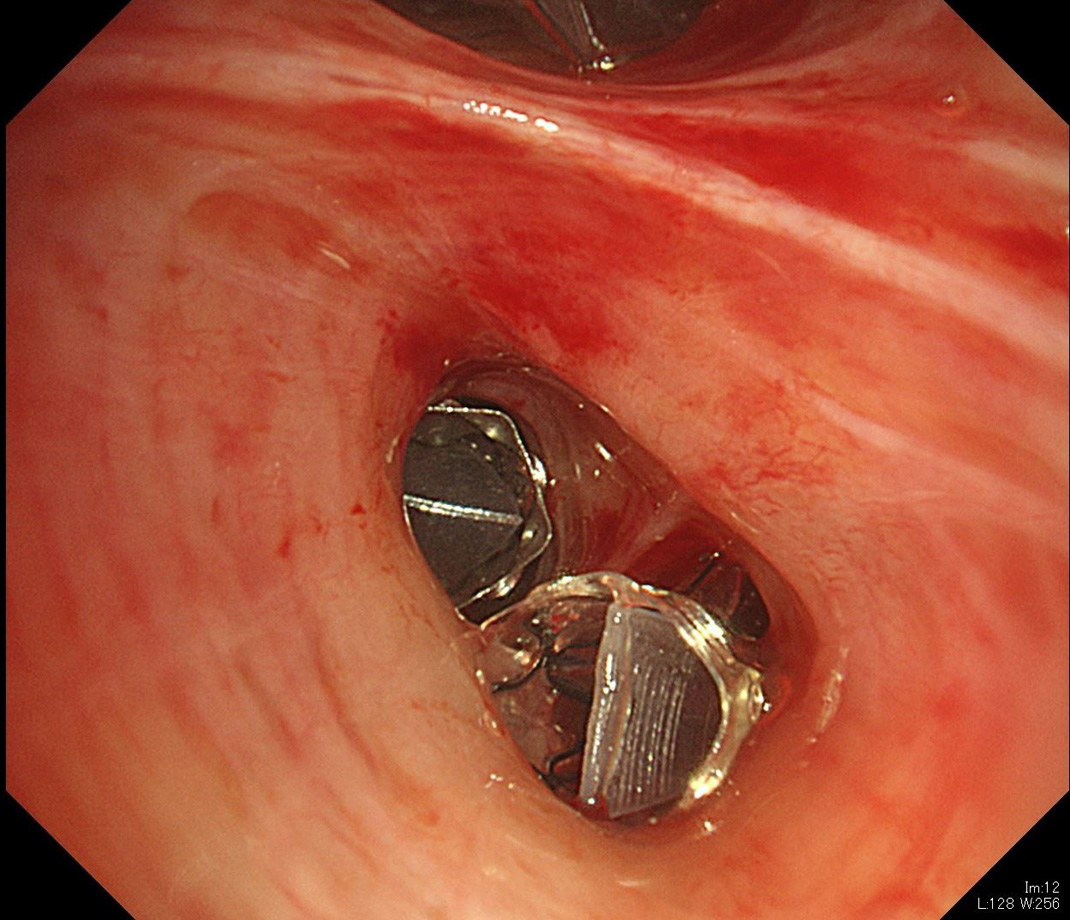

図5 気管支バルブ:標的気管支に気管支バルブが留置されています。